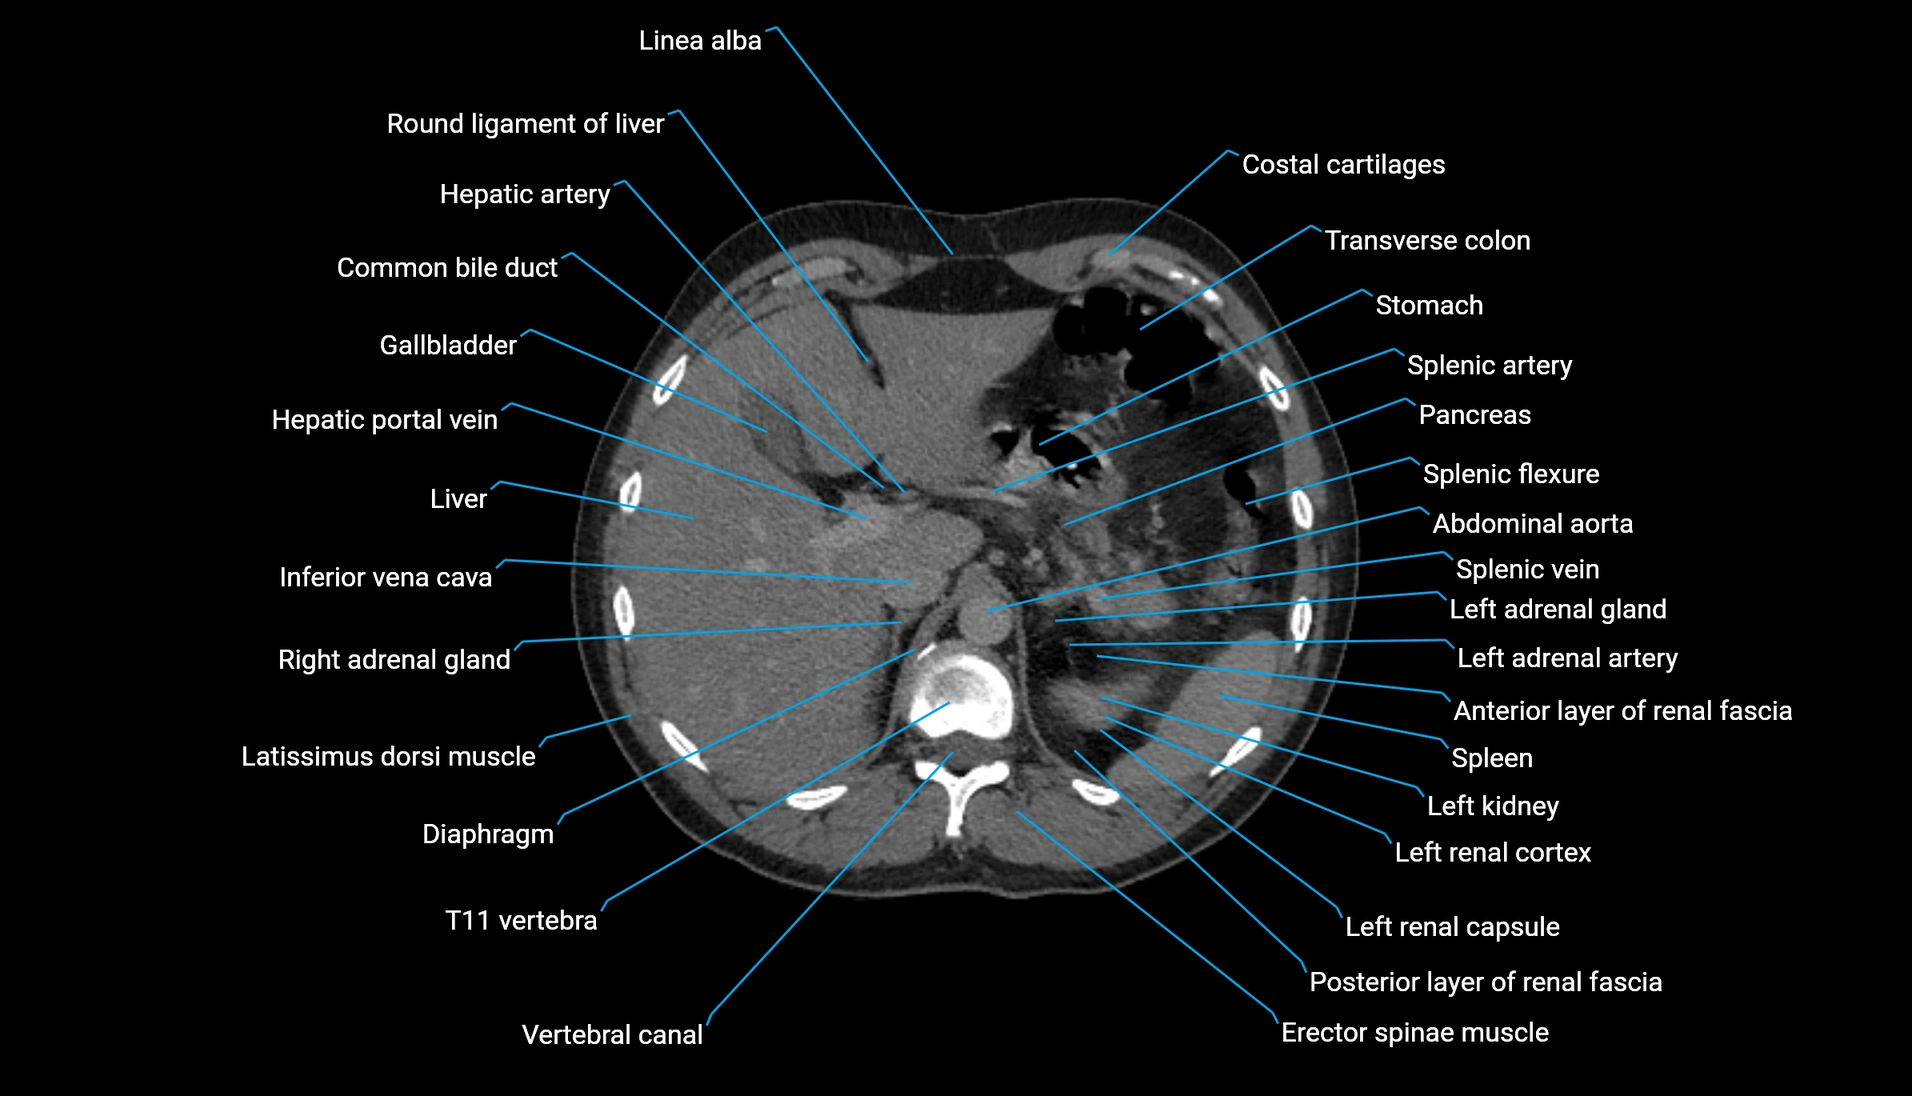

CT Appearance

Non-contrast CT:

-

Demonstrates cortical bone of acetabular rim in excellent detail

Detects fractures, dysplasia, retroversion, or bony overcoverage (pincer impingement)

3D reconstructions used in preoperative hip surgery planning

CT VRT 3D image

CT image